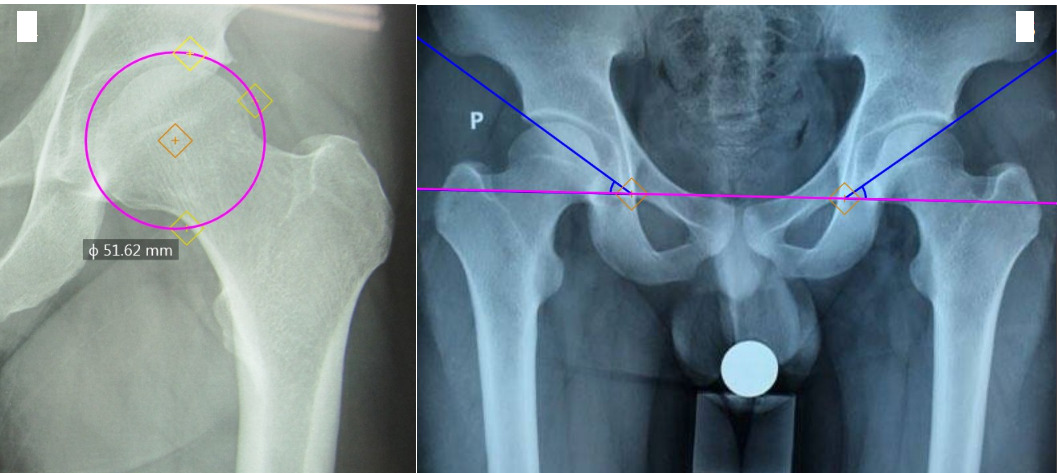

Acetabular diameter: is the diameter of the circle with an arc that fits into the acetabular socket (Figure 1A).

Acetabular tilt angle: is the angle formed by two straight lines, one passing through the lower medial bone edge (teardrop) of the acetabulum on both sides and one passing through the upper edge of the acetabulum and the lower medial bone edge (teardrop) of the acetabulum on the same side (Figure 1B).